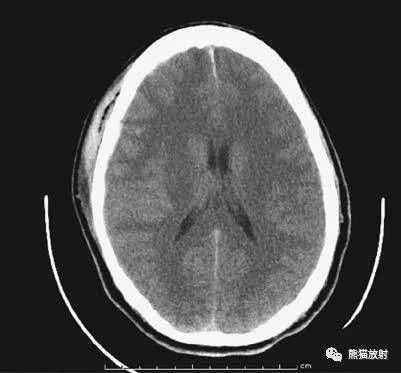

5、侧脑室体部层面

由额、颞、枕叶构成,两侧侧脑室体部之间为透明隔,外侧为尾状核和体部。侧脑室后角(枕角)可不对称,室内可见脉络丛钙化。中线处可见大脑纵裂池和大脑镰。